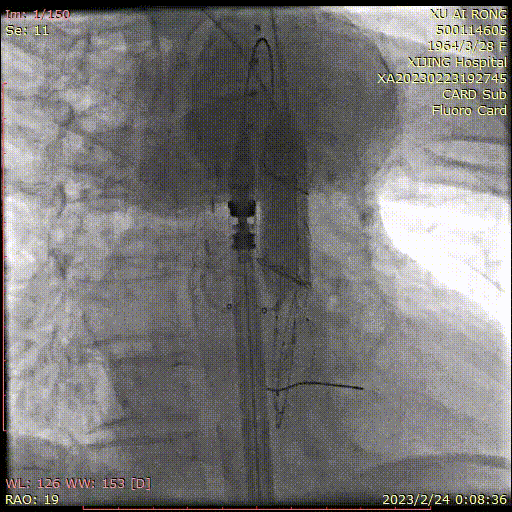

主体支架释放后造影

主体支架窗口

与分支动脉开口存在偏差

利用自适应性成功超选左颈总动脉,并置入分支支架

利用自适应性成功超选无名动脉,并置入分支支架

利用自适应性成功超选左锁骨下动脉,

并置入分支支架

术后造影

术后CTA